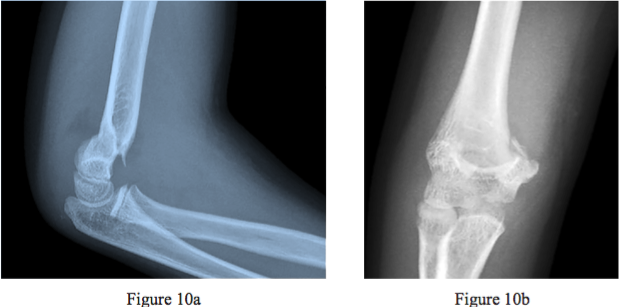

Question 10 Figures 10a and 10b are the radiographs of a 6-year-old girl who fell on her outstretched right hand. What is the best next step?

1- Closed reduction and casting of the supracondylar humeral fracture

2- Closed reduction and pinning with 2 or 3 laterally introduced pins of the supracondylar humeral fracture

3- Closed reduction and pinning with 2 laterally introduced pins and 1 medially introduced pin of the supracondylar humeral fracture

4- Open reduction and pinning of the supracondylar humeral fracture with 2 or 3 laterally introduced pins

5- Open reduction and pinning of the supracondylar humeral fracture with 2 laterally introduced pins and 1 medially introduced pin